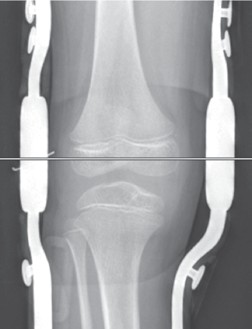

An der unteren Extremität ist der Therapiealgorithmus ähnlich, wobei hier das Ziel nicht darin besteht, spezifische Funktionen zu erreichen, sondern durch gestreckte Hüften, Knie und Füße in plantigrader Stellung das Stehen und Gehen zu ermöglichen. Während des ersten Lebensjahres sind die tägliche Physiotherapie oder Dehnungsübungen durch die Eltern sowie die Anlage von Gipsredressionsschälchen in Korrekturstellung über die Nacht die wichtigsten Therapieformen 14. Ab dem ersten Lebensjahr kommen dann auch an den Beinen Nachtlagerungsorthesen mit Quengelgelenken zum Einsatz. Auch hier ist es wiederum entscheidend, dass sowohl die Gipsschälchen als auch die Orthesen zumindest 6 von 24 Stunden, besser länger, angelegt werden, um eine entsprechende Redression und Korrektur zu erzielen 15. Ziel der Behandlung ist letztendlich – je nach Ausprägung der Arthrogrypose – die Erreichung bzw. der Erhalt der Sitz‑, Steh- und Gehfähigkeit. Auch an der unteren Extremität werden die Orthesen mit separaten Fassungen für Oberschenkel, Unterschenkel und Füße angefertigt. Letztere werden im Wachstumsalter ringförmig gefasst, um den hohen Kräften entgegenzuwirken und ein Rutschen zu verhindern (Abb. 2). Auch an den Kniegelenken werden vorwiegend Caroli-Quengelgelenke eingebaut und radiologisch deren Position überprüft (Abb. 3). Die Orthesengelenke am Kniegelenk sollten im Röntgen in der Mitte der Femurepiphyse zu liegen kommen (Abb. 4).

Die Therapie von Kindern mit einer Arthrogrypose ist umfangreich. Der Kinderorthopäde leitet die Behandlung bereits in den ersten Lebenstagen mit täglicher Physiotherapie und häuslichen Dehnübungen ein. Während im ersten Lebensjahr v. a. Gipsschälchen angepasst werden, kommen ab dem ersten Lebensjahr Orthesen zum Einsatz, die jeweils mindestens 6 von 24 Stunden getragen werden müssen, da ansonsten die Kontrakturen im Wachstum zunehmen. Die Orthesen an der oberen Extremität werden mit separaten möglichst ringförmigen Fassungen für Oberarm, Unterarm und Hand angefertigt. Auch an den Beinen bekommen sowohl Ober- als auch Unterschenkel eine separate Fassung. Die Füße werden ringförmig gefasst. Über den Gelenken werden Quengelgelenke eingebaut, deren Lage radiologisch überprüft werden muss. Ziel ist der Erhalt von Gelenkbeweglichkeit und ‑funktion und damit die Förderung der Selbstständigkeit und des Selbstbewusstseins.